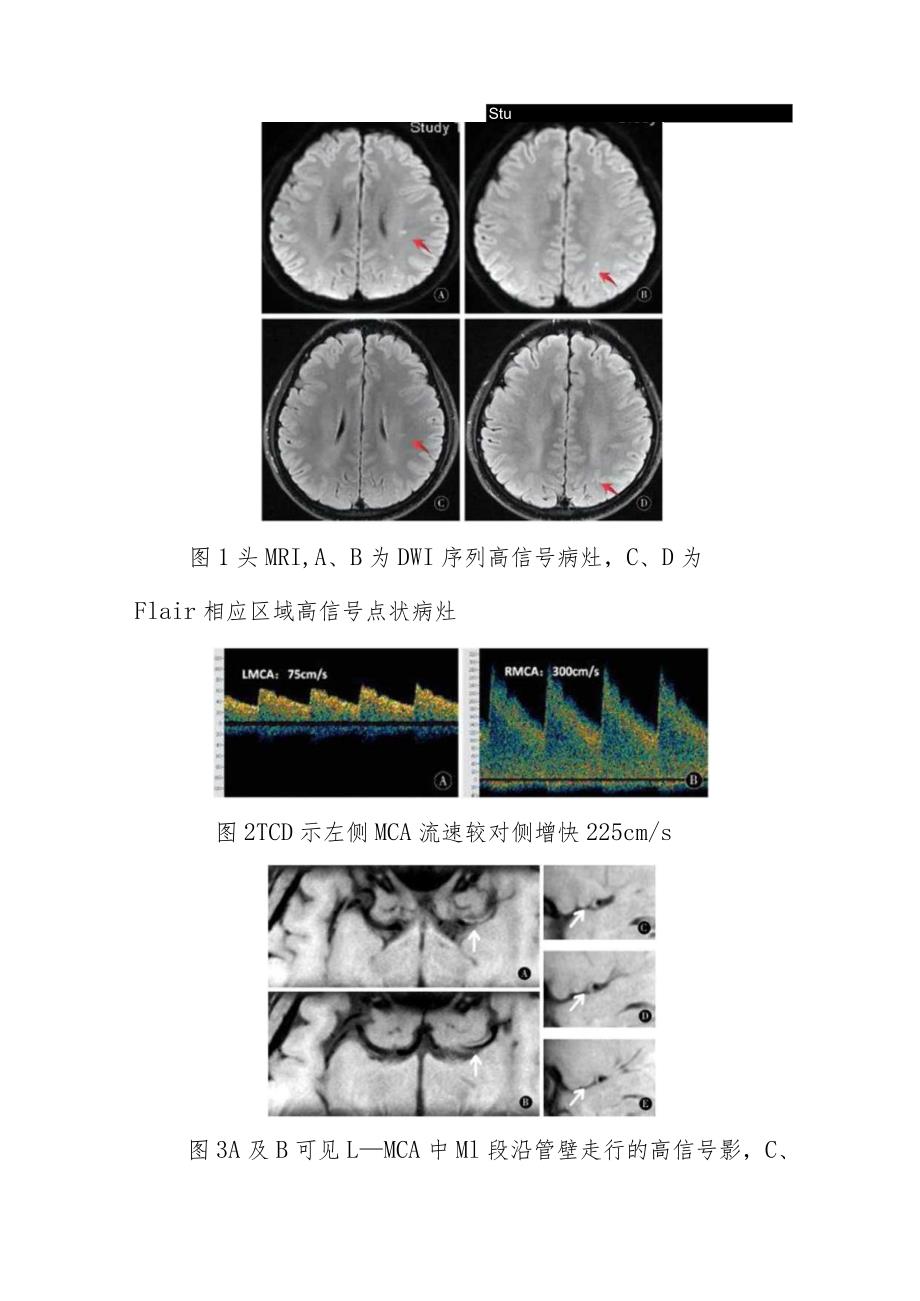

3、齐;腹软;双下肢无水肿;神清语利,脑神经未见明显异常,肢体肌力5级,双侧病理征阴性;予头部CT平扫(20160824)未见异常;头部MRl(2016-08-25)示,左侧脑室旁、半卵圆中心放射冠DWI点状高信号,T2及Flair可见相应区域高信号影,Tl等信号,脑室系统未见异常,脑沟脑裂无异常,中线居中(图1);TCD检查(20160826)示左侧MCA血流速度大于对侧,发泡实验结果阴性(图2);颅脑MRA+HRMRI斑块分析示,左侧MCA狭窄,Ml段管壁处可见斑块形成影(图3);颈动脉及椎动脉CTA检查(20160828)未见颅外段颈动脉及椎动脉异常;心电图回报未见异常;超声心动未见心瓣膜病

4、、左心耳附壁血栓形成及黏液瘤,射血分数65%;血尿常规、肝肾功、电解质、心肌酶、凝血功能、血糖、甲功五项、感染四项、感染四项、ESR、CRP.Hcy均未见异常;血脂:甘油三酯5.28mmolL,低密度脂蛋白3.59mmolLoStu图1头MRI,A、B为DWI序列高信号病灶,C、D为Flair相应区域高信号点状病灶图2TCD示左侧MCA流速较对侧增快225cm/s图3A及B可见LMCA中Ml段沿管壁走行的高信号影,C、I)、E中斑块分析可见管壁处向管腔内生长的“新月形”致密斑块影,未见斑块溃疡本例患者青年男性,以短暂性脑缺血发作(Transientischemicattack,TIA)形式起病